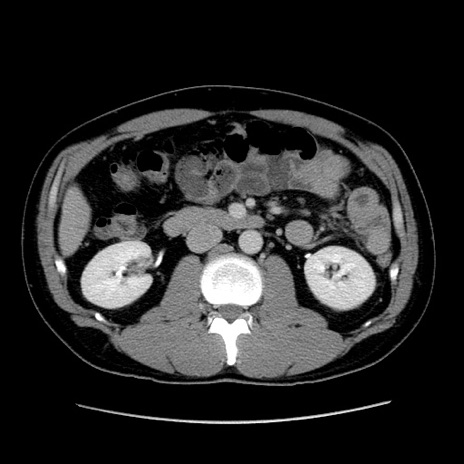

冠状断像

症例4(横断像)

【症例】30歳代男性

【主訴】腹痛、嘔吐

【現病歴】昨晩から突然の腹痛あり、その後嘔吐、軟便も出現。腹痛が改善しないため救急搬送となる。2日前にしめ鯖の食事歴あり。

【身体所見】意識清明、苦悶様、BP 135/90mmHg、BT 35.7℃、腹部:平坦、やや硬、心窩部〜臍部に自発痛、圧痛あり、筋性防御+、反跳痛-

【データ】WBC 8100、CRP 0.57